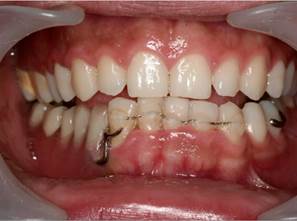

Ten years after being admitted to the service, the patient has referred good adherence to surgical treatment and subsequent follow-up. The mandibular reconstruction is in excellent conditions in relation to the integration of its free graft, functionality and aesthetics. Finally, the removable prosthetic rehabilitation is in place and functional, which was used instead of osseointegrated implants due to financial reasons mainly (Figure 3).